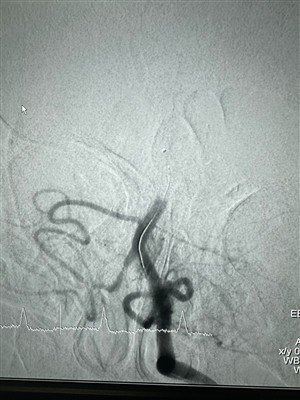

Případy použití tekutého embolického systému LAVAPodělte se o nedávnou intervenční operaci, která byla dokončena pomocí systému LAVA Liquid Embolic System společnosti NeuroSafe.

Nové pouzdro pro bagrovací stent retrieverNedávno došlo k úspěšnému případu trombektomie pomocí dredgerského stentového retrívru společnosti NeuroSafe Medical Co., Ltd. Dredger stentový retrívr má neinvazivní měkkou špičku, která výrazně s...

Nové pouzdro používá hloubkový retrívr stentu48-letý muž s akutní pravostrannou hemikarézou v okně trombektomie (4 hodiny). Před a po trombektomii pomocí Dredgerova stentového retrieveru (30x30) v průběhu rami terminalis superiores a inferiores.

Vzrušující případ v SRH Waldklinikum Gera Dne 11. dubna 2024!V SRH Waldklinikum Gera byl nedávno proveden zajímavý případ pod vedením Dr. med. Kroeßner. Tento případ zahrnoval použití Gluttonova aspiračního katétru (6F) spolu s dredgerovým stentem Retriever ...